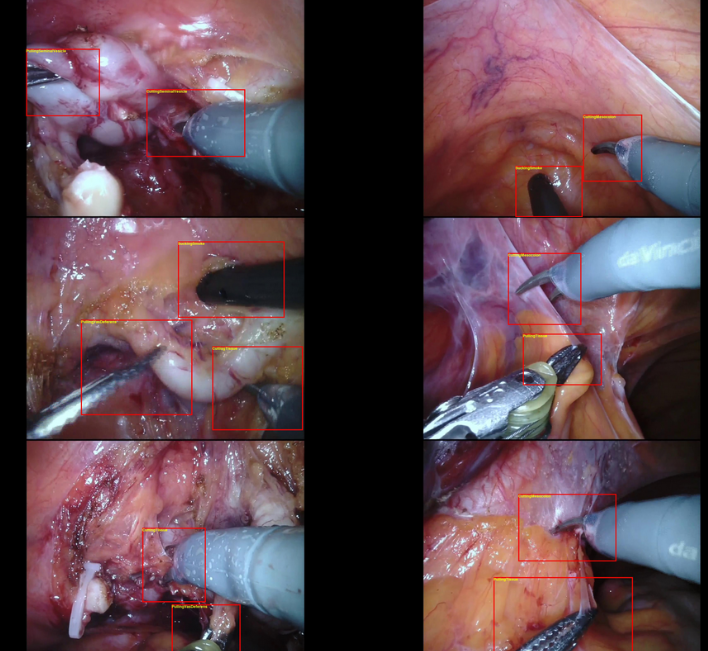

SARAS-MESAD

| 名称 | 标注内容 | 类型 | 模态 | 数量 | 标签格式 | 文件格式 | License |

|---|---|---|---|---|---|---|---|

| SARAS-MESAD | 24种动作 | 静态背景动作识别 | 内窥镜 | 4(真实手术)+5(模拟手术) | CC BY-NC-SA 4.0 |

| SARAS-ESAD | 21种手术动作 | 静态背景动作识别 | 内窥镜 | 22,601(训练)+4,574(测试) | 图片 | BB | CC BY-NC-SA |